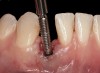

Problem: The implant is placed too facial with significant recession on the midfacial aspect of the abutment and/or crown; the implant is healthy and the patient has a high smile line with an intermediate to thick periodontal phenotype (Figure 1 and Figure 2).17-19

Solution: Decoronate the implant by placing a surgical cover screw on it and allow the soft tissues to migrate over the coronal aspect (implant decoronation).8,20,21 A few weeks later, perform the second-stage uncovering of the implant and place a flat profiled healing or custom abutment to redirect the submergence profile or angle of the provisional crown.22 After maturation of the peri-implant mucosal soft tissues several weeks later, make the final impression and construct the definitive restoration with compensatory flat subgingival contours to allow midfacial soft-tissue stability.

Fig 1. Midfacial recession can affect the esthetics of a smile and lead to an unsatisfactory outcome.

Fig 2. The cause for midfacial recession is excessive labial implant placement. Secondary to poor placement is overcontouring of the implant abutment.